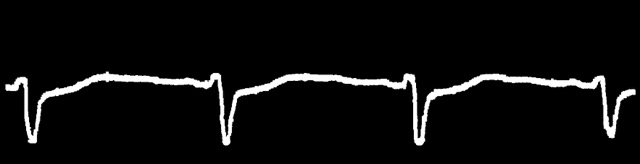

105 ECG Strips. 16 Categories.

From normal sinus rhythm to complex arrhythmias — annotated ECG strips with clinical context, difficulty grading, and structured interpretation guidance.

Try three real clinical scenarios from the ECG Atlas. Use the clinical context to reason through each rhythm — then check your interpretation against the structured explanation.

Full 12-lead ECG strip with clinical context and patient demographics.

Systematic approach: rate, rhythm, axis, P waves, PR, QRS, ST, QT.

Structured explanation with key diagnostic features and clinical significance.